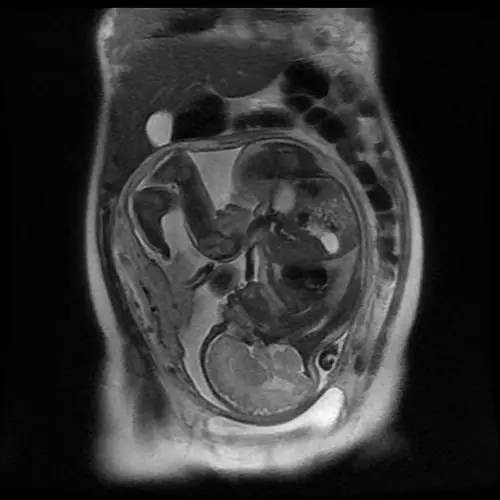

核磁共振效应最早是用于观察晶体内部结构的,后来被聪明的科学家移植到了人体身上。这不仅是因为核磁共振能精致的绘出人体的细微结构,而且还在于核磁共振没有电离辐射,对任何娇嫩的人体组织都不会有伤害。所以核磁共振能看到肚子里宝宝甜美的睡容。